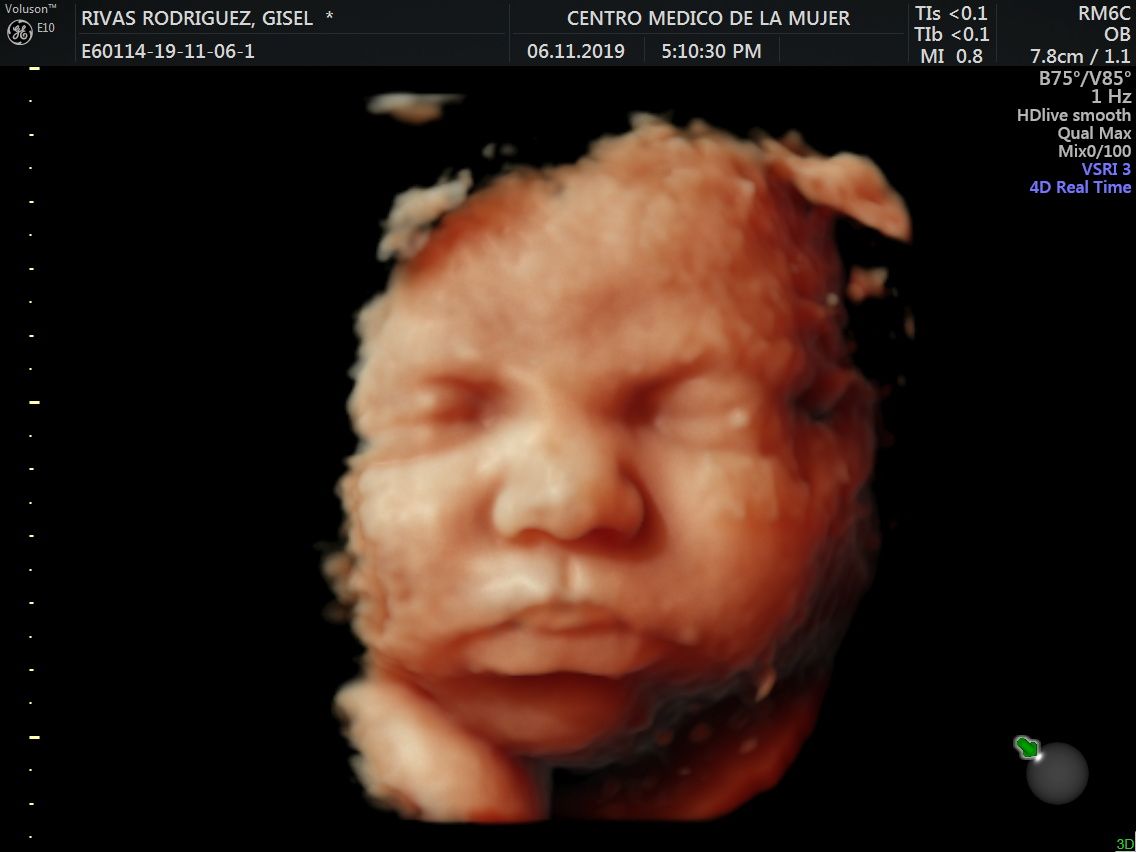

Fotos y videos

ECO Anatómico

Consiste en la evaluación especifica de cada organo y sistema del bebé con medidas detalladas de cada parte para evaluar su crecimiento proporcional.